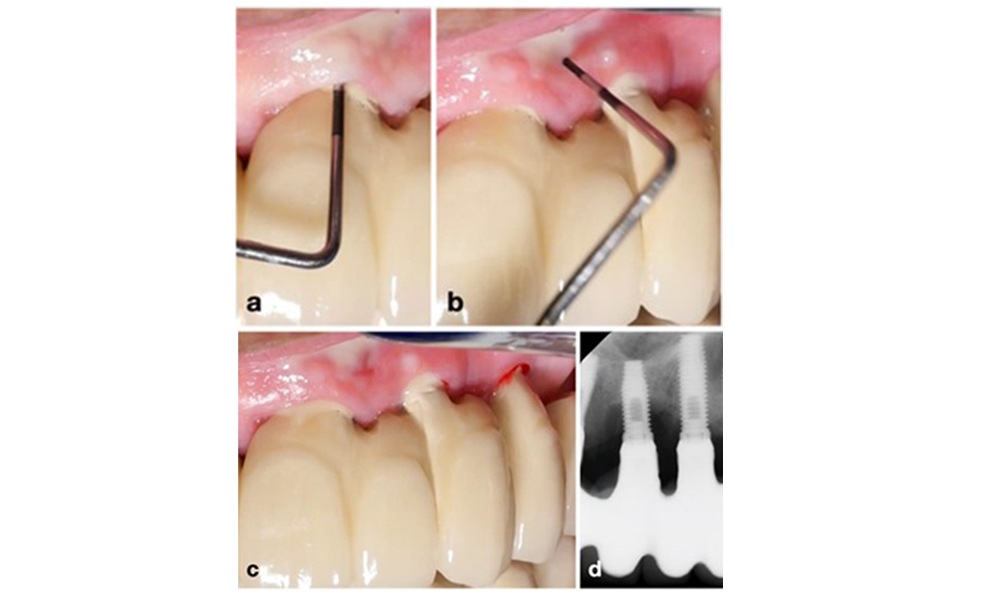

Management of peri-implantitis at implants judged as treatable consists of a non-surgical phase, which is often followed by surgical intervention. For the non-surgical approach, similar measures as those applied for the treatment of peri-implant mucositis are used; based on laboratory experiments air-polishing devices with a subgingival nozzle appear to provide certain advantages in terms of biofilm removal, compared to hand- or ultrasonic instruments (Herrera et al. 2023; Moharrami et al. 2019; Ronay et al. 2017) (figure 9).

Patient case with peri-implantitis. The non-surgical treatment is performed by using the supragingival (a-b) and subgingival handpiece of an air-polishing device (c-d). Removing the supra-construction provides better access to the implant surface (d).

Figure 9. Patient case with peri-implantitis. The non-surgical treatment is performed by using the supragingival (a-b) and subgingival handpiece of an air-polishing device (c-d). Removing the supra-construction provides better access to the implant surface (d).